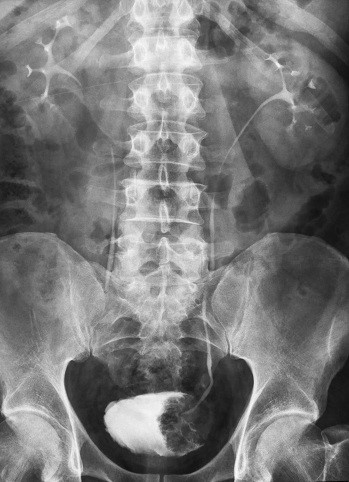

Обзорная урограмма захватывает всю почечную область с двух сторон. На ее основе можно составить заключение о строении, положении и состоянии почек мочевого пузыря и мочеточников.

Процедура проводится в качестве первичного исследования, позволяя уточнить положение и размеры почек, визуализировать тени, подозрительные на камни.

Если обзорная урограмма показала изменения, то для ее уточнения врач назначает рентген с контрастированием или, как называют это исследование специалисты, экскреторную урографию.

Этот метод является ведущим в диагностировании камней в почках и мочеточниках.

В этом случае применяется обзорное исследование. Оно позволяет определить размер и форму камней, а также их приблизительное местонахождение.

Не каждый камень даст тень на рентгеновском снимке. Степень его отображения зависит от химического состава конкремента — оксалаты и фосфаты дают густую тень, а ураты, цистины и ксантины вообще не видно на снимке.

Если обнаружена подозрительная тень вне мочевых путей, то она может оказаться камнем в желчном пузыре или обызвествленным лимфатическом узлом.